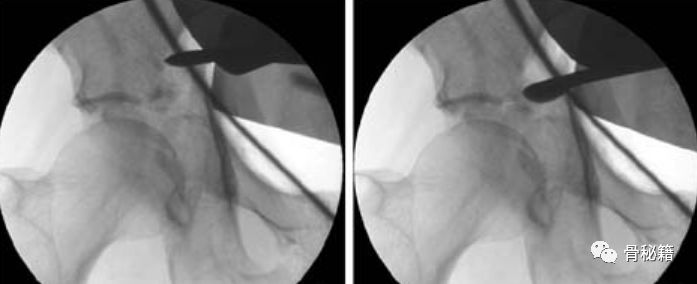

选用合适的手术器械进行复位,同时辅助透视

我们做髋臼的时候一般是做臼不见臼,没有办法从里面看到关节面是否复位。通过把压缩的关节面用骨拨进行翘拨来进行复位。

有骨折线的时候直接用骨拨复位。

没有骨折线的时候,通过开窗后用尖顶来复位。